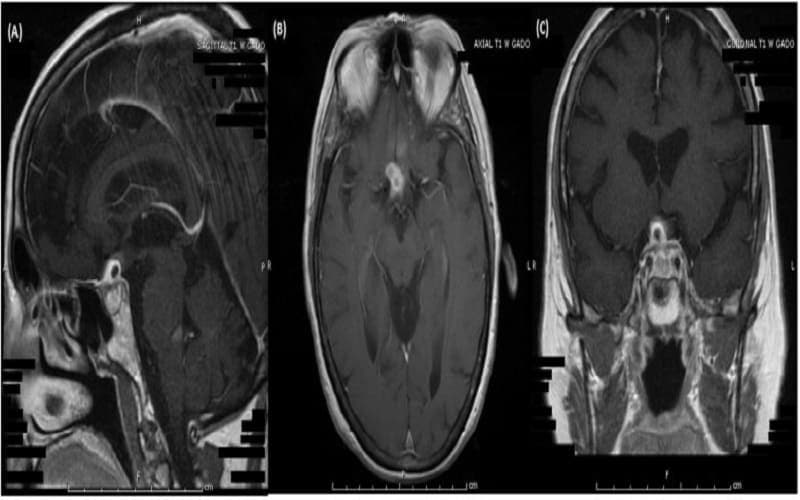

2.4. Chẩn đoán hình ảnh (MRI tuyến yên)

Song song với xét nghiệm suy tuyến yên, chụp cộng hưởng từ (MRI) được sử dụng để quan sát cấu trúc tuyến yên và vùng xung quanh. MRI giúp phát hiện u tuyến yên, u nang, viêm hoặc bất thường giải phẫu có thể gây suy giảm chức năng. Trong trường hợp khối u lớn, bác sĩ có thể chỉ định thêm kiểm tra thị lực để đánh giá ảnh hưởng lên dây thần kinh thị giác.